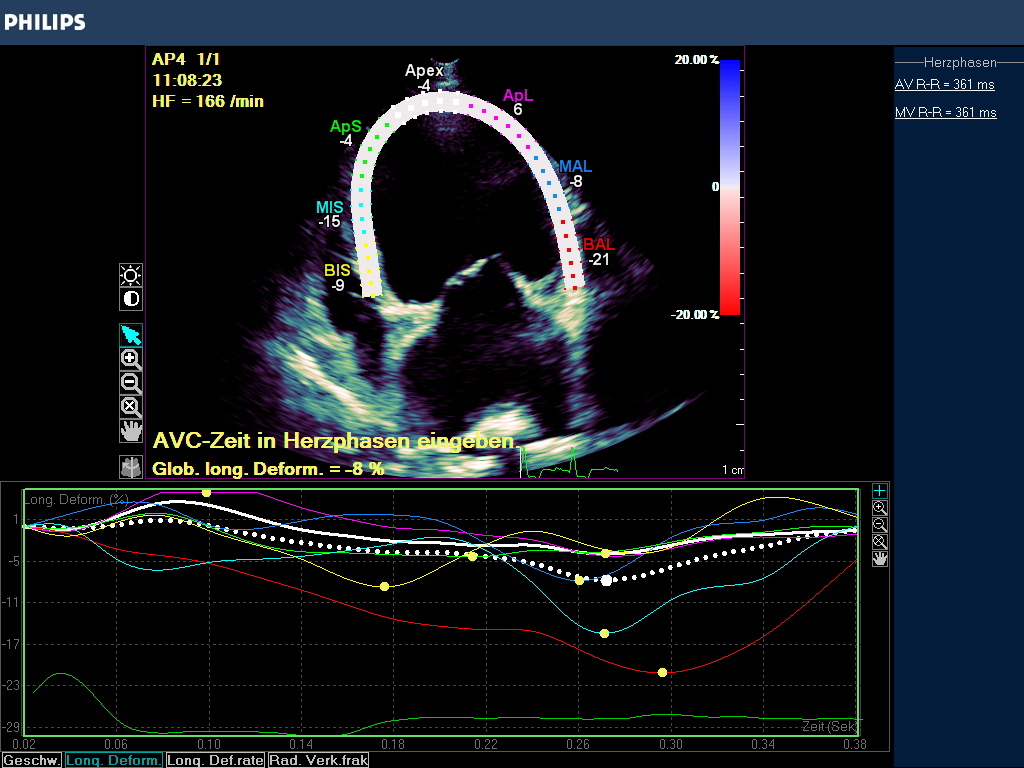

In praxi wird das Myokardium (LV/RV oder Atrien) in 7 Segmente unterteilt, die z.B. für den linken Ventrikel eine Hufeisenform annehmen, die Grenzen dieser enddiastolischen Region Of Interest (ROI) können manuell korrigiert werden über die Software des Geräts. Erfasst wird die endokardiale -, epikardiale Grenze und die myokardiale Mittellinie. Die Akquise der Werte erfolgt automatisch, semiautomatisch oder manuell. Die Einbeziehung des Perikardiums kann zu einer Reduzierung der Strainwerte führen! Die ROI Segmente bekommen Farben und Kürzel zugeordnet (Tabelle 1, Abb.2), die für Myokardsegmente stehen und so können nicht nur globale sondern auch regionale Dysfunktionen erkannt werden.

Der Gerätemonitor gibt die Strainmessergebnis in Form einer Kurve an , deren wellenförmige Line den Farbsegmenten entspricht und die zeitliche Veränderung der Strain beurteilbar macht. Jede ROI hat auch hier ihre definierte Farbe und der Durchschnittswert wird in einer globalen Strain Kurve als weiße Punktlinie angezeigt. Der Anteil der einzelnen Segmente an der GS ist abhängig von ihrer Größe. Das Maximum der globalen Strain GS wird als globale longitudinale Strain definiert (GLS).

Das Ergebnis der GLS wird in negativ -%- Zahlen angegeben. In besonders schwer erkrankten Fällen kann die Zahl positiv werden! Je höher die negative Zahl angegeben wird desto stärker ist die Verformung bzw. Kinesie des Muskels. Darüber hinaus wird nach der Simpson Methode eine Ejektionsfraktion ermittelt , die in EF % angegeben wird (Abb. 3).

Globale Dysfunktion des linken Ventrikels durch Dilatation bei einer DKM oder infolge eines Ductus botalli persisitens oder einer chronischen Aorteninsuffizienz können bei hochgradigen Befunden sehr niedrige oder gar positive Strainzahlen hervorbringen. Die Ejektionsfraktion ist in diesen Fällen i.d.R. vermindert (Abb. 3).